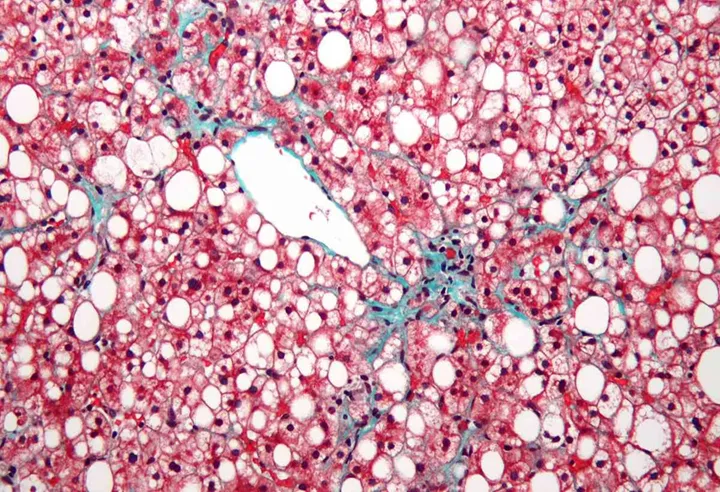

Genom den så kallade ESPRESSO-studien, där leverbiopsier från alla Sveriges patologavdelningar samlats in, identifierade forskarna alla barn och unga vuxna födda efter 1992 som efter vävnadsprovtagning fått diagnosen icke-alkoholrelaterad fettlever (NAFLD), totalt 165 individer.

Barnen hade en medianålder på 12 år, drygt 60 procent var pojkar och närmare hälften hade svår fettlever med leverfibros. Kontrollgruppen bestod av barn och unga utan fettlever som matchats efter kön och ålder.

Fettlever ger ofta inga besvär och många har det utan att veta om det, men sjukdomen kan ibland leda till inflammation i levern och skrumplever. Mängden fett som ansamlas i levern kan minskas genom viktnedgång och goda vanor som fysisk aktivitet.